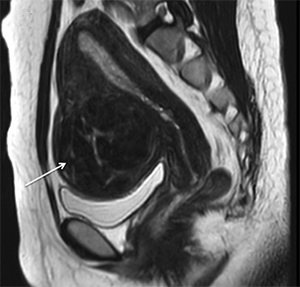

МРТ міоми

МРТ: вузол міоми на передній стінці матки

Лейоміома матки також може бути підтверджена за допомогою комп'ютерної томографії (КТ) і магнітно-резонансного дослідження (МРТ). Це також безболісні діагностичні процедури, що дають точну інформацію про кількість, структуру і розташування вузлів міоми.